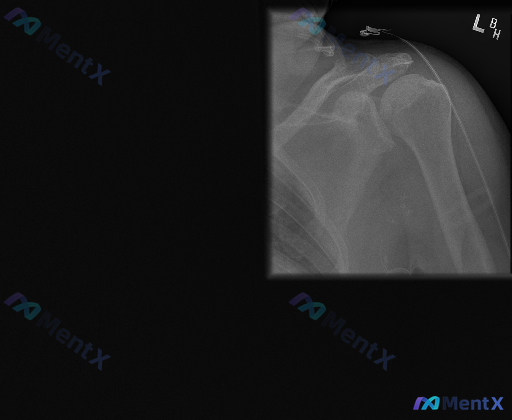

整理到一张左肩部X光正位片的读片资料,有点意思,放出来大家一起过一遍思路: 基础影像所见(骨骼部分): - 肱骨近端、肩胛骨、锁骨远端骨性结构完整,未见明确皮质中断、脱位或骨质破坏 - 骨密度大致均匀,盂肱关节、肩锁关节对位可 但有一个非常明确的异常: 在肩峰上方的软组织区域,可见一段呈弧形走行的线...